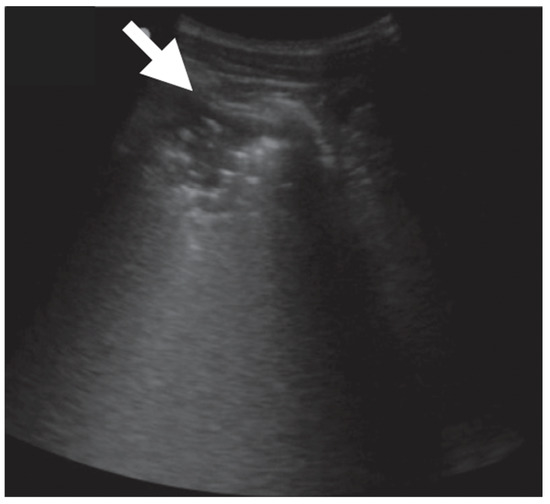

- Rea, G.; Sperandeo, M.; Lieto, R.; Bocchino, M.; Quarato, C.M.I.; Feragalli, B.; Valente, T.; Scioscia, G.; Giuffreda, E.; Foschino Barbaro, M.P.; et al. Chest Imaging in the Diagnosis and Management of Pulmonary Tuberculosis: The Complementary Role of Thoracic Ultrasound. Front. Med. 2021, 8, 753821. [Google Scholar] [CrossRef]

- Giannelli, F.; Cozzi, D.; Cavigli, E.; Campolmi, I.; Rinaldi, F.; Giachè, S.; Rogasi, P.G.; Miele, V.; Bartolucci, M. Lung ultrasound (LUS) in pulmonary tuberculosis: Correlation with chest CT and X-ray findings. J. Ultrasound 2022, 25, 625–634. [Google Scholar] [CrossRef]